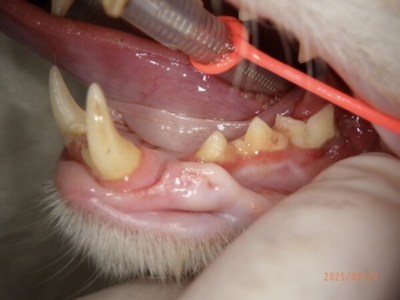

歯肉口内炎の猫ちゃん。喉の奥まで赤くなっている

同じ猫ちゃんの全臼歯抜歯後。犬歯切歯は残し残りの歯を抜歯。奥の腫れが改善している

重度の歯肉口内炎のねこちゃん

全顎抜歯で改善した

1歳の猫ちゃん。歯肉口内炎。